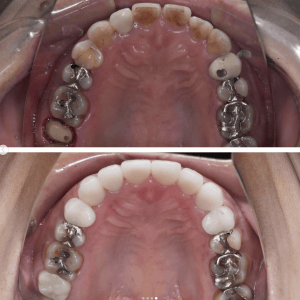

Case004 – ワイヤー矯正

上下左右4本の抜歯を行い、全体の歯並びを矯正した症例です。